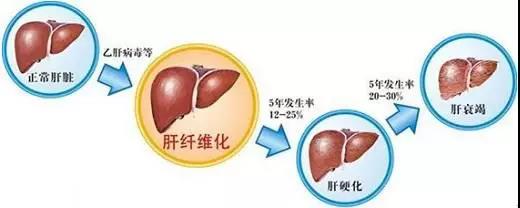

肝硬化(liver cirrhosis,LC)是临床常见的慢性进行性肝病,也是各种慢性肝病发展的晚期阶段。具体表现为肝细胞弥漫性变性坏死,继而出现纤维组织增生和肝细胞结节状再生,这三种改变反复交错进行,结果肝小叶结构和血液循环途径逐渐被改建,使肝脏变形、变硬而导致肝硬化。该病早期无明显症状,后期则出现一系列不同程度的门静脉高压和肝功能障碍,直至出现上消化道出血、肝性脑病等并发症死亡。

我们常听到「中国人的肝,外国人的肺」,意思就是说,西方肺病发病率高,中国肝病发病率高。我国是全球肝硬化发病率、死亡率最高的国家。